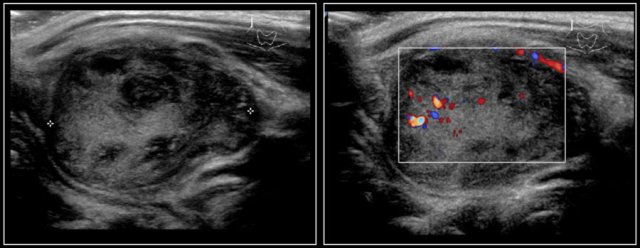

The images are of a fourteen-year-old boy with a painless swelling in the left neck.

The ultrasound shows several enlarged hypoechoic lymhnodes, that lack an hyper-echoic hilum.